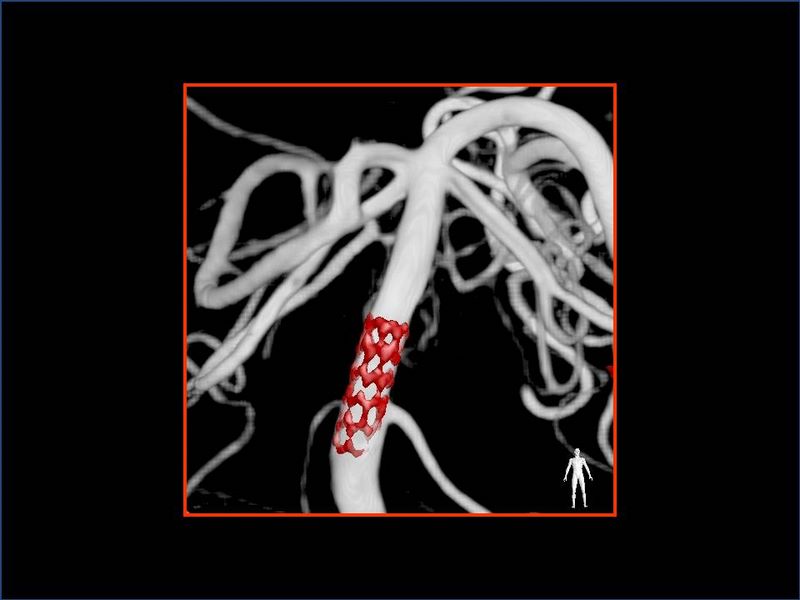

Estenosis Basilar